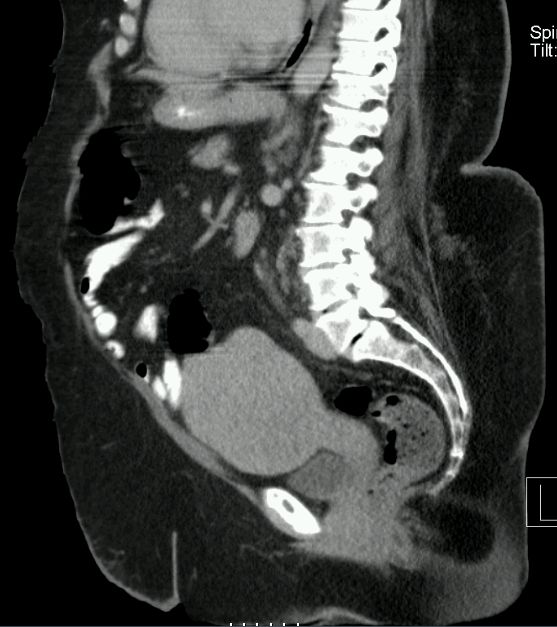

81-jährige Patienten mit Endometriumkarzinom von 23 Jahren. Jetzt ossäre Metastase des vorderen rechten Schambeins mit pathologischer Fraktur. Zystische Raumforderung dorsal seit 8 Jahren unverändert.